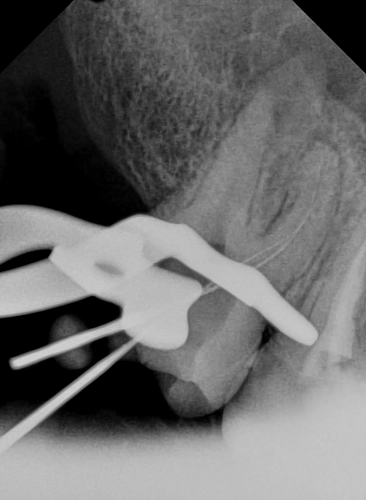

На фото представлен клинический случай. Пациент обратился в нашу клинику с жалобой на боль при надкусывании . При первичной диагностике был выявлен сломанный инструмент в корневом канале, который привёл к воспалению .